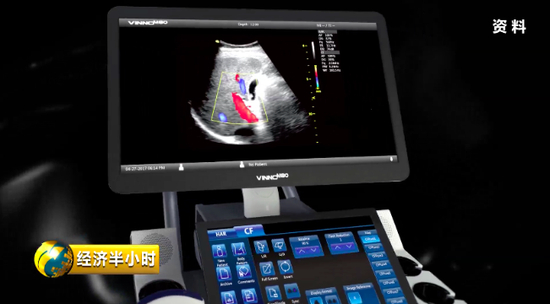

“彩超”,人们并不陌生,但是既能诊断又能帮助治疗的“彩超”对大多数人来说却是陌生的。

有一个特殊的彩色B超设备,不仅能够精确诊断,还能帮助大夫有效地给予患者治疗。也就是说,在治疗疾病时,在超声波的介入下,药物被精准送达病变位置,释放药物,从而实现靶向治疗。而且这个彩色B超设备副作用很少,安全性特别好。《经济半小时》记者在苏州工业园区了解到,目前这种彩色B超设备在国际上已经达到一流水平。

显示速率越快,意味着成像效果越好,医生的诊断和治疗也会更精确。公司研发总监高文友告诉记者,他们一代数据处理平台的速度可以理解成 5G 速度的 10 倍,而目前开发出来的二代产品,传输带宽比上一代高了将近150倍;成像显示的速率,也将近快了一百倍以上。

2014年,公司靠着自主创新,终于研制出具有完全知识产权、性能达到世界一流水平的彩色B超设备。

彩色B超设备